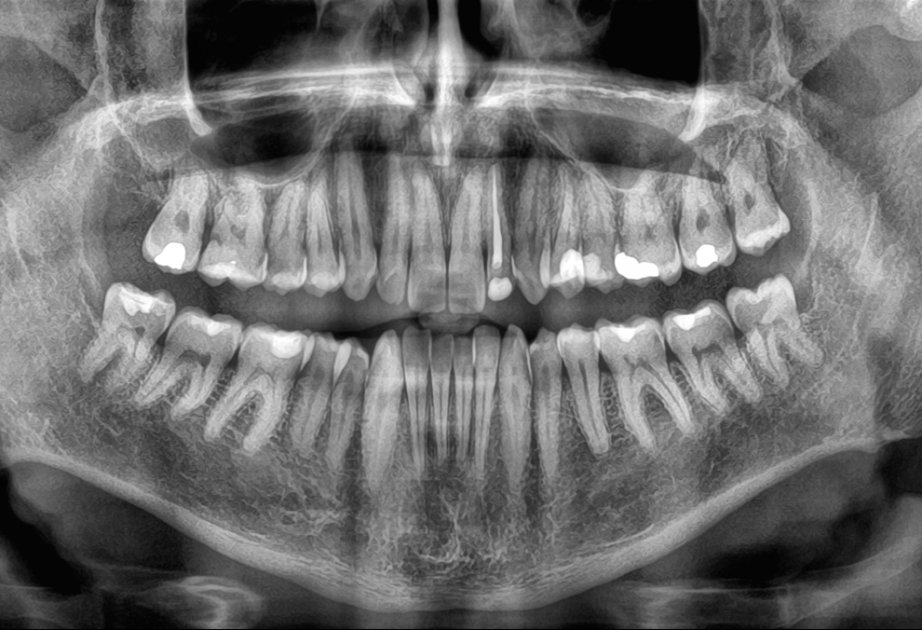

Araşdırma: Diş itkisi ölüm riskini artıra bilər

Yeni bir araşdırma göstərib ki, yaşlı insanlarda dişlərin sürətlə itirilməsi ölüm riskinin artması ilə əlaqəlidir. Çinli alimlər 3,5 il ərzində 8073 yaşlı insanı izləyərək belə nəticəyə gəliblər.

AZƏRTAC “sciencealert.com” portalına istinadla xəbər verir ki, tədqiqatın nəticələrinə görə, dişlərin itirilmə sürəti nə qədər yüksəkdirsə, bütün səbəblərdən ölüm riski də bir o qədər artır. Bu əlaqə yaş, cins, təhsil, içki və məşq vərdişləri kimi digər amillər nəzərə alındıqdan sonra da qalır. Mütəxəssislər bildirirlər ki, dişlərin itirilməsi birbaşa ölümə səbəb olmur, lakin diş itkisinə yol açan sağlamlıq problemləri, məsələn, iltihab, pis qidalanma və ürək xəstəlikləri ömrü qısalda bilər. Alimlər diş itkisinin insanın ümumi sağlamlıq vəziyyətini qiymətləndirmək üçün göstərici kimi istifadə oluna biləcəyini vurğulayırlar. Həkimlər dişlərin qorunması üçün müntəzəm diş həkimi müayinəsini, gündə iki dəfə fırçalamağı və siqaretdən uzaq durmağı tövsiyə edirlər.